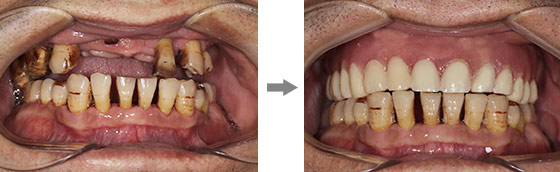

李大爷由于没有保护好牙齿,再加上长期有抽烟的习惯,导致牙齿逐渐松动脱落,由于多颗牙缺失影响饮食后李大爷无奈戴上了活动假牙,然而假牙并没有解决李大爷的问题,很多东西不能咬,此外几年后李大爷仍有几颗牙相继下岗,最终导致半口牙全军覆没。

活动假牙使用起来非常不方便,在朋友的介绍下李大爷来到南京康贝佳口腔医院,想试试经常在报纸上看到的种植牙。

康贝佳胡主任为李大爷做了详细的口腔检查,并采用了ALL-ON-4技术,整个手术过程仅仅30分钟,只需4颗植体就恢复了半口牙,不仅创伤小、疼痛轻,恢复快,且为李大爷省了近一半的费用。

种牙后的李大爷表示以前一直怕种牙疼,现在种完才知道几乎没有疼痛感,后悔没早点来种牙,现在晚年幸福终于有了很大的保障,想吃什么就吃什么。